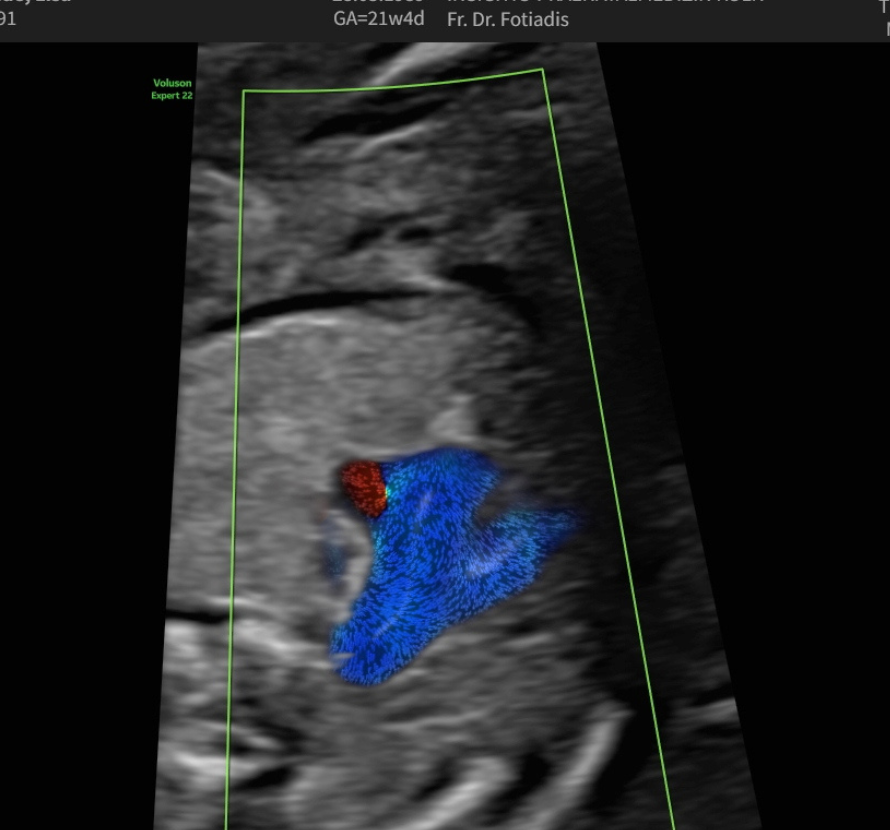

Echokardiographie

Fehlbildungen des Herz-Kreislaufsystems gehören zu den häufigsten Störungen des Neugeborenen und finden sich bei 0,5–1 % aller lebend geborenen Kinder.

Viele dieser Herzfehler sind nicht schwerwiegend und bedürfen keiner Therapie. Ein Teil jedoch kann gravierend, ja sogar lebensbedrohend bei der Geburt sein, sodass hier die Diagnose schon im Mutterleib lebensrettend sein kann. In diesen Fällen muss dann die Entbindung geplant in einem Zentrum mit den Neonatologen und Kinderkardiologen stattfinden, das Neugeborene benötigt bestimmte Medikamente oder muss intensivmedizinisch betreut werden. Manchmal sind auch sehr schnell Eingriffe und Operationen nötig.

Das Entdecken und die Beurteilung von fetalen Herzfehlern erfordert ein hohes Maß an Untersuchungserfahrung und eine entsprechende Geräteausstattung, sodass sie häufig im Rahmen von Routineuntersuchungen nicht erkannt werden. Daher sollten gerade Eltern mit einem erhöhten Risiko für fetale Herzfehler diese Untersuchung des kindlichen Herzens durchführen lassen.